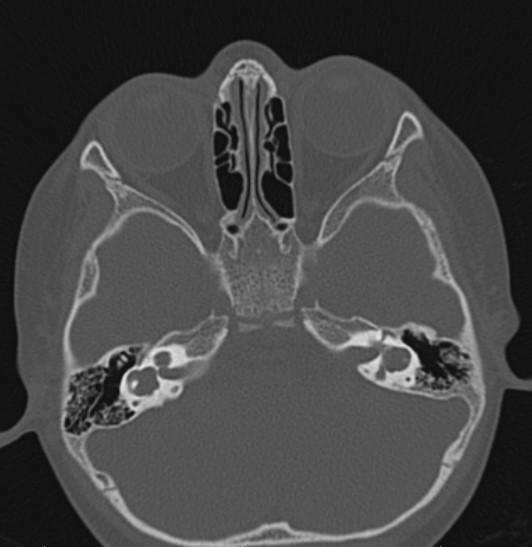

*2-year-old child with hearing loss.

Answer: Bilateral incomplete partition Type I (cystic cochleovestibular anomaly)

Axial MR and CT images show the cystic bilateral cochlea (red arrow) and the dilated cystic bilateral vestibule (yellow arrow). The vestibular aqueduct is normal in size.